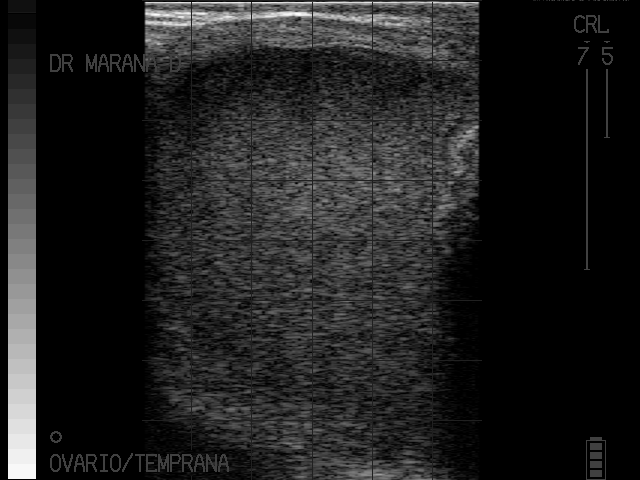

La detección de anomalías anatómicas y fisiológicas en el tracto reproductivo de la hembra.

Solamente pueden diagnosticarse y confirmarse por medio de la palpación rectal y el apoyo del ecógrafo, resultado de esto podemos hacer tratamientos específicos y facilitar la toma de decisiones.

imagenes cortesia:

MVZ MsC David Maraña Peña Especialista en Reproducción Bovina